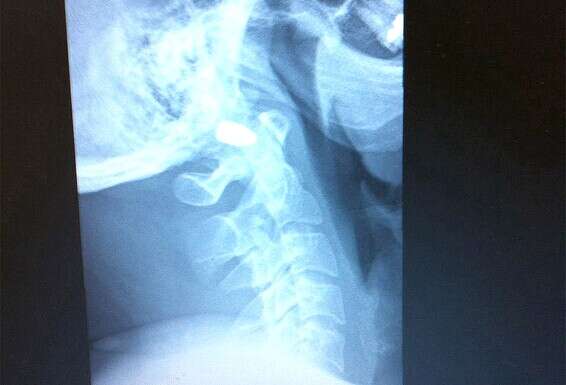

הרופאים הצליחו לייצב את מצבו של אסף, אבל החליטו לא להוציא את הקליע מראשו, משום שנתקע בין החוליה הראשונה של עמוד השדרה לקודקוד של הראש, צמוד לעורק ראשי ולעצבים. "הם הגדירו את זה 'שני מילימטר ממוות'".

הכדור עדיין נמצא שם?

"כן, הם לא יודעים לומר אם זה יסכן אותי בהמשך. אני במעקב, עושה CT כל שנה. זה קצת מכעיס אותי, כי אני רוצה לדעת מה מצבי, אבל אני מבין שזה מצב נדיר, ופשוט אין הרבה מידע על זה".